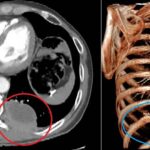

Si tratta di un uomo di 67 anni, residente nella provincia dell’Aquila, colpito da un voluminoso tumore polmonare sinistro che aveva infiltrato strutture ossee e muscolari della parete toracica fino a raggiungere la cute. Dopo un percorso di chemioterapia e immunoterapia neoadiuvante, effettuato per ridurre la massa e rendere possibile la chirurgia, il paziente è stato sottoposto a una complessa procedura operatoria. Il trattamento chirurgico ha previsto la rimozione del tumore mediante lobectomia polmonare inferiore sinistra, la demolizione della porzione di parete toracica infiltrata, con asportazione delle strutture coinvolte (coste, muscoli e cute), e la successiva ricostruzione parietale attraverso il posizionamento di una protesi biologica ADM (Acellular Dermal Matrix) nella sede priva delle costole. A completamento della riparazione è stato effettuato il trasferimento di un lembo muscolo-cutaneo destro, utilizzando il muscolo gran dorsale controlaterale, così da ricostituire l’integrità anatomica e funzionale della parete toracica.

A distanza di tre mesi dall’intervento, il paziente gode di buona salute ed è libero da malattia. La Tac post-operatoria evidenzia la piena integrazione della protesi con le strutture osteo-muscolari, confermando il completamento del processo di riparazione. La prestazione ad alta specializzazione ha permesso di eradicare del tutto il tumore e di ripristinare un’adeguata qualità di vita, con un risultato ottimale sotto il profilo funzionale ed estetico.